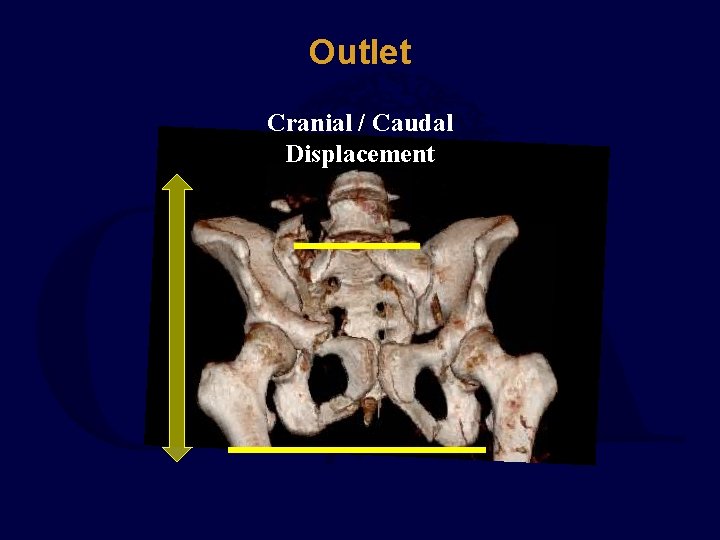

Outlet Cranial / Caudal Displacement